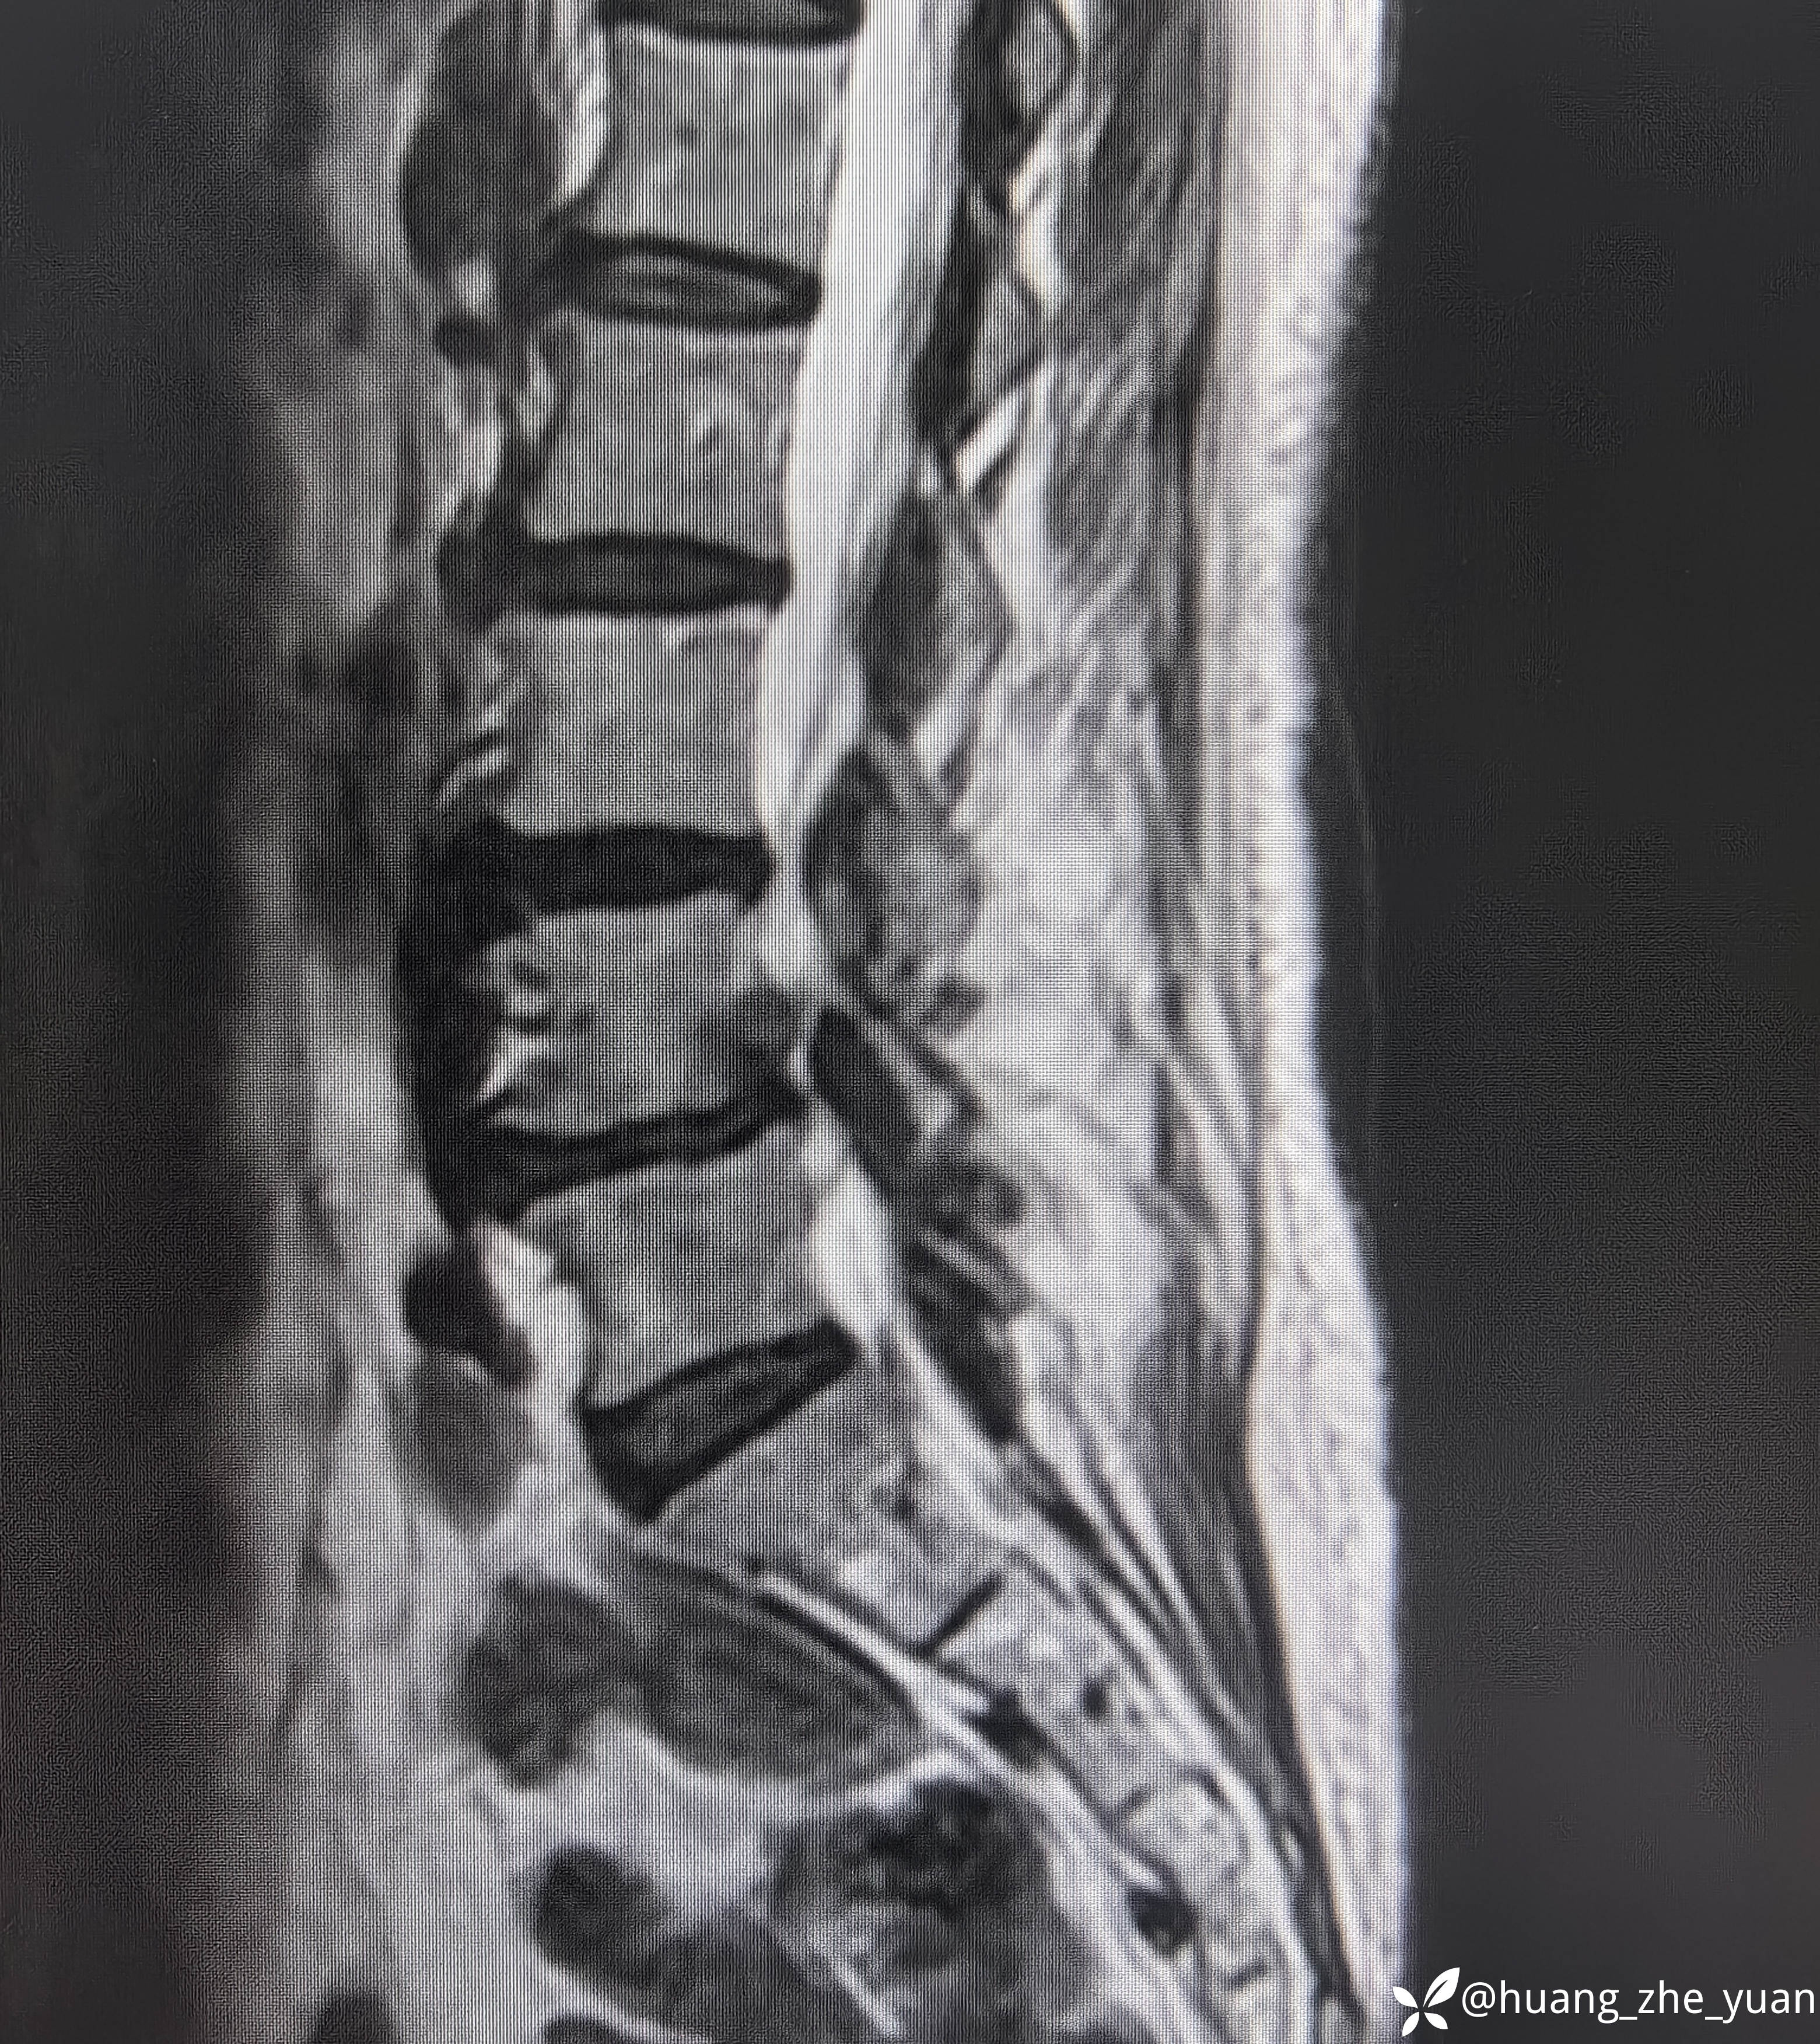

70岁女性,反复右下肢放射痛八个月。合并症:糖尿病,胰岛素泵控制。